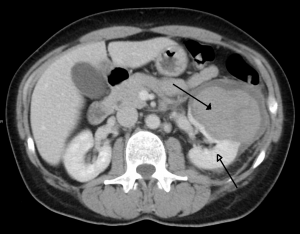

Left kidney injury (open arrow) with retropeitoneal hematoma (closed arrow).